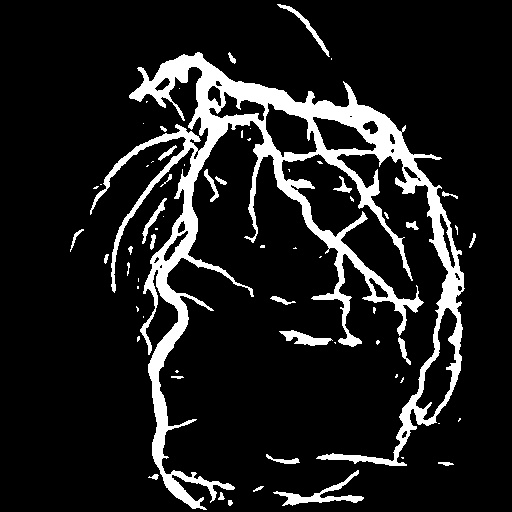

| Image | Ground truth | Video frame | Ground truth | Video frame | Ground truth |

| XCAD [33] | CADICA [19] | Our XACV dataset | |||

4.1 XACV Dataset

We collect 111 complete records of coronary artery X-ray videos, encompassing the injection, flow through the blood vessels around the heart, and dissipation of the contrast agent. Subsequently, we establish the XACV (X-ray Angiography Coronary Video) dataset. Each video consists of varying numbers of high-resolution coronary artery X-ray images. We invite experienced radiologists to annotate the vascular regions, focusing on one or two frames where the contrast agent is most prominent in each video. The XCAD dataset contains only a single image, and the CADICA video dataset does not provide corresponding ground truth. Therefore, in the following experiments, we conduct all the analyses on our collected XACV dataset and the corresponding GT for each sequence. In Figure 5, we show that compared to other publicly available datasets, XCAD [33] and CADICA [19], our dataset exhibits finer annotations in the vascular regions, providing an advantage for future related tasks. The development and use of our dataset have been approved by our institution’s IRB.